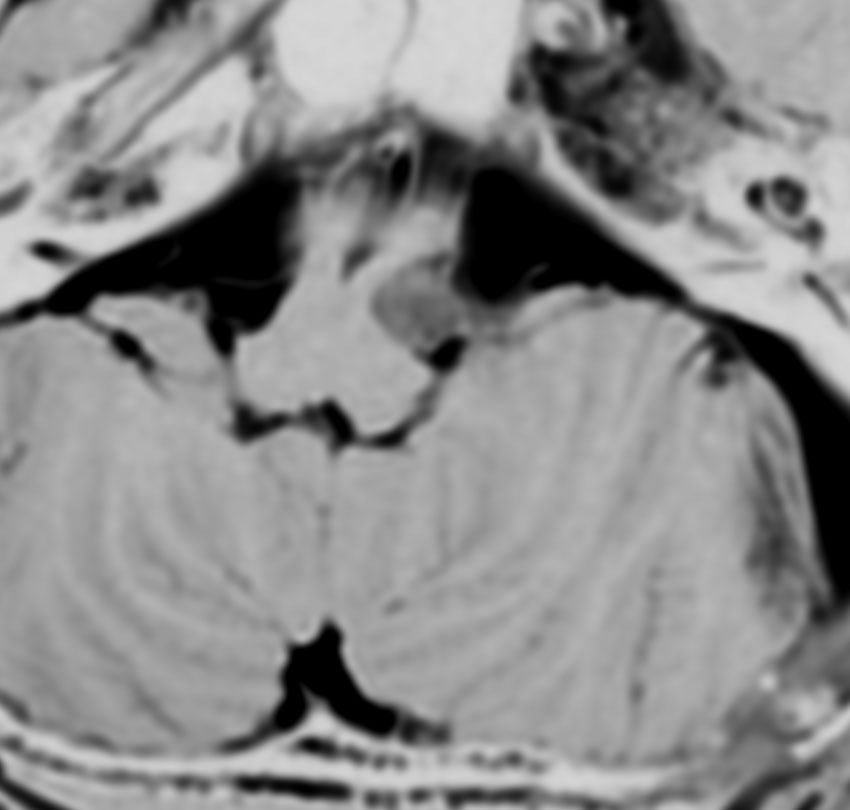

脊髄根 spinal rootから発生した無症候性の副神経鞘腫です。神経根は脊髄前根からでて脊髄の外側から背側へと上行するので,脊髄を横から圧迫するようになります。

徐々に増大しました。手術摘出を行うときに副神経を温存できないと,胸鎖乳突筋と僧帽筋の麻痺が生じます。